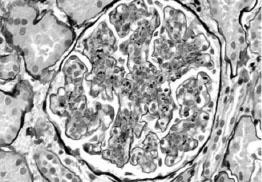

光镜下,大多数患者肾小球呈内皮细胞、系膜细胞弥漫性急性增殖,少数以渗出病变为主,另有少部分呈系膜、毛细血管型病变(膜增殖型病变),严重时增生的系膜可将肾小球分隔成小叶状,偶有球囊新月体形成。电镜可见上皮下电子致密物呈驼峰状沉积,为本病的特征。但这一变化消失较快,发病3个月后即不易见到,这些沉积物多在上皮侧,有时在内皮下。免疫荧光检查,内含有免疫球蛋白,主要是IgG、IgM、IgA也可见到,同时也可有C3沉积,有时尚可见到链球菌抗原在系膜区沉积物中。见图2—1、图2—2、图2—3。

图2—1 毛细血管内增生性肾小球肾炎,肾小球内皮和系膜细胞增生,中性粒细胞浸润(PASM x400)